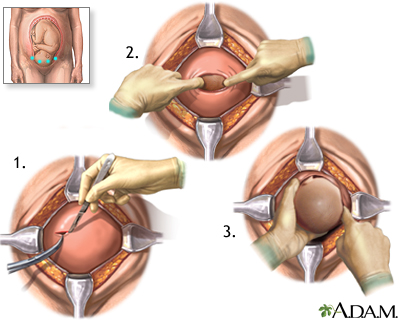

Your provider will carefully consider the risk of bleeding against early delivery of your baby. After 36 weeks, delivery of the baby may be the best treatment.

Nearly all women with placenta previa will need a C-section. If the placenta covers all or part of the cervix, a vaginal delivery can cause severe bleeding. This can be deadly to both the mother and baby.

An emergency C-section may be done if the bleeding is heavy and cannot be controlled.